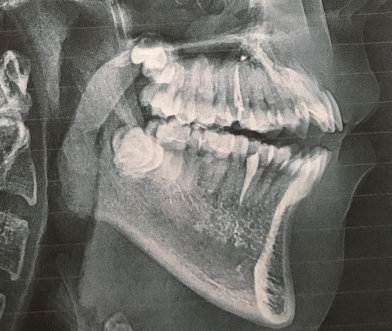

После снятия брекетов носил пластинку около 1 год 5 месяцев на ночь. К вечеру чувствовал, что пластинка садится туго, к утру все нормально. В 15 лет заметили, что прикус открытый. Сделали панорамный снимок. Определили, что 8-ки неправильно расположены в челюсти.

Через полтора года сделали еще один панорамный снимок, корни уже почти сформированы. Все стоматологи говорят, что нужно удалять 8-ки. Еще есть КТ. Сегодня были на консультации у стоматолога-хирурга. Он сказал, что очень сложно, но можно удалить пока один зуб снизу слева. Верхние предложил пока не трогать, подождать, когда они ближе подойдут.

Нужно ли удалять 8-ки (сейчас внизу)? Что делать с верхними 8-ми? Может ли удаление 8-ок немного расслабить зубной ряд, и хоть как то улучшить прикус?

В обязательном порядке требуется повторное эндодонтическое лечение. Восьмые зубы удалять надо, но, важно определить, не расположены ли верхние на границе с верхнечелюстной пазухой, а нижние в нижнечелюстном канале. Определить это можно по трехмерному снимку. Если зубы лежат в области этих анатомических образований, то необходимо подождать и провести удаление позже. Но требуется коррекция открытого прикуса.